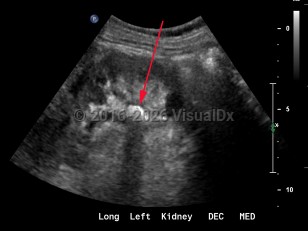

Renal calculus

Although asymptomatic stones are frequently discovered with radiographic imaging, the most common presentation is sudden-onset flank pain radiating to the groin, accompanied by nausea and vomiting. This colicky pain (renal colic) typically waxes over the course of 15-30 minutes and becomes steady, unrelenting, and unbearable. Patients may experience worsening paroxysms of pain lasting 20-60 minutes as the stone courses downward through the ureter and as the ureter spasms. If the stone's descent is arrested at the ureterovesical junction, patients may experience urinary frequency, dysuria, and urgency and are predisposed to the development of urinary tract infections both from the stone forming as a nidus for bacterial growth and from the mechanical urothelial trauma caused by the stone's movement. Most individuals with nephrolithiasis will also develop hematuria, particularly when passing a stone.